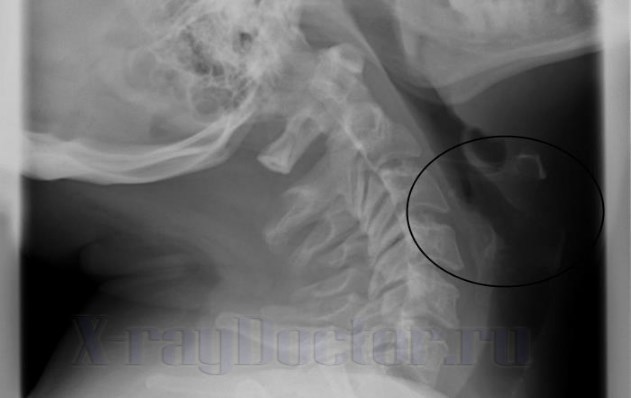

На боковой рентгенограмме можно четко проследить следующие анатомические структуры:

- хрящи;

- переднюю и заднюю стенку глотки;

- гортанные желудочки;

- черпалонадгортанные связки.

На рентгенограмме в боковой проекции можно увидеть полосы просветления, которые указывают на сужения просвета трахеи и глотки. Передняя стенка органа начинается от корня языка. Данная анатомическая структура относится к группе мягких тканей, через которые рентгеновские лучи проходят насквозь.

На уровне 3-го шейного позвонка располагается подъязычная кость, которую рентген показывает только при ее обызвествлении.

Аденоиды на снимке в боковой проекции прослеживаются нечетко. При выполнении дополнительного исследования (томографии) можно четко проследить увеличение глоточных миндалин. С помощью томографических срезов прослеживается структура органов на разных уровнях.